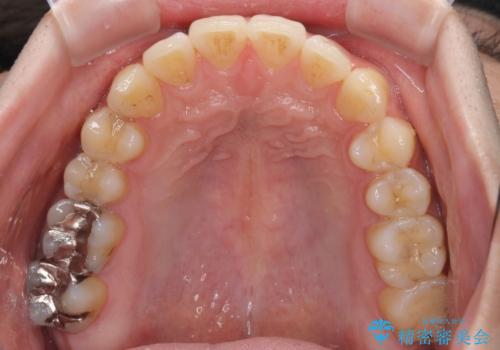

インビザライン・ライトによる矯正治療の後戻り改善

再矯正後の後戻りを防ぐため、歯列排列後に、下顎前歯はワイヤーによる固定を行いました。

下顎前歯の歯列を動かないようにしておくことで、上顎前歯の後戻り防止にも効果を発揮します。